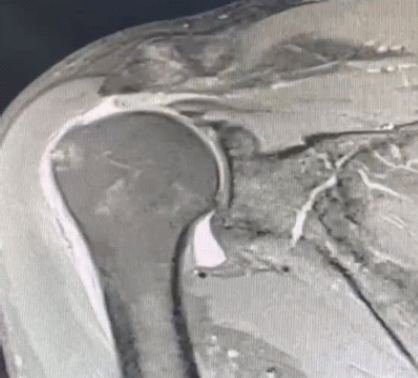

The surgical technique commences with the patient positioned in the lateral decubitus position, followed by the establishment of standard arthroscopic portals to facilitate diagnostic evaluation and subsequent repair [6]. After a comprehensive diagnostic arthroscopy, typically performed through the standard posterior viewing portal, the surgeon evaluates the extent of the rotator cuff tear and any associated pathologies. We then proceed to clear the subacromial space thoroughly, ensuring optimal visualization of the massive rotator cuff tear to be addressed (Fig. 1).

Figure 1: Magnetic resonance imaging showing full-thickness tear of supraspinatus and infraspinatus tendon with grade 2 retraction.